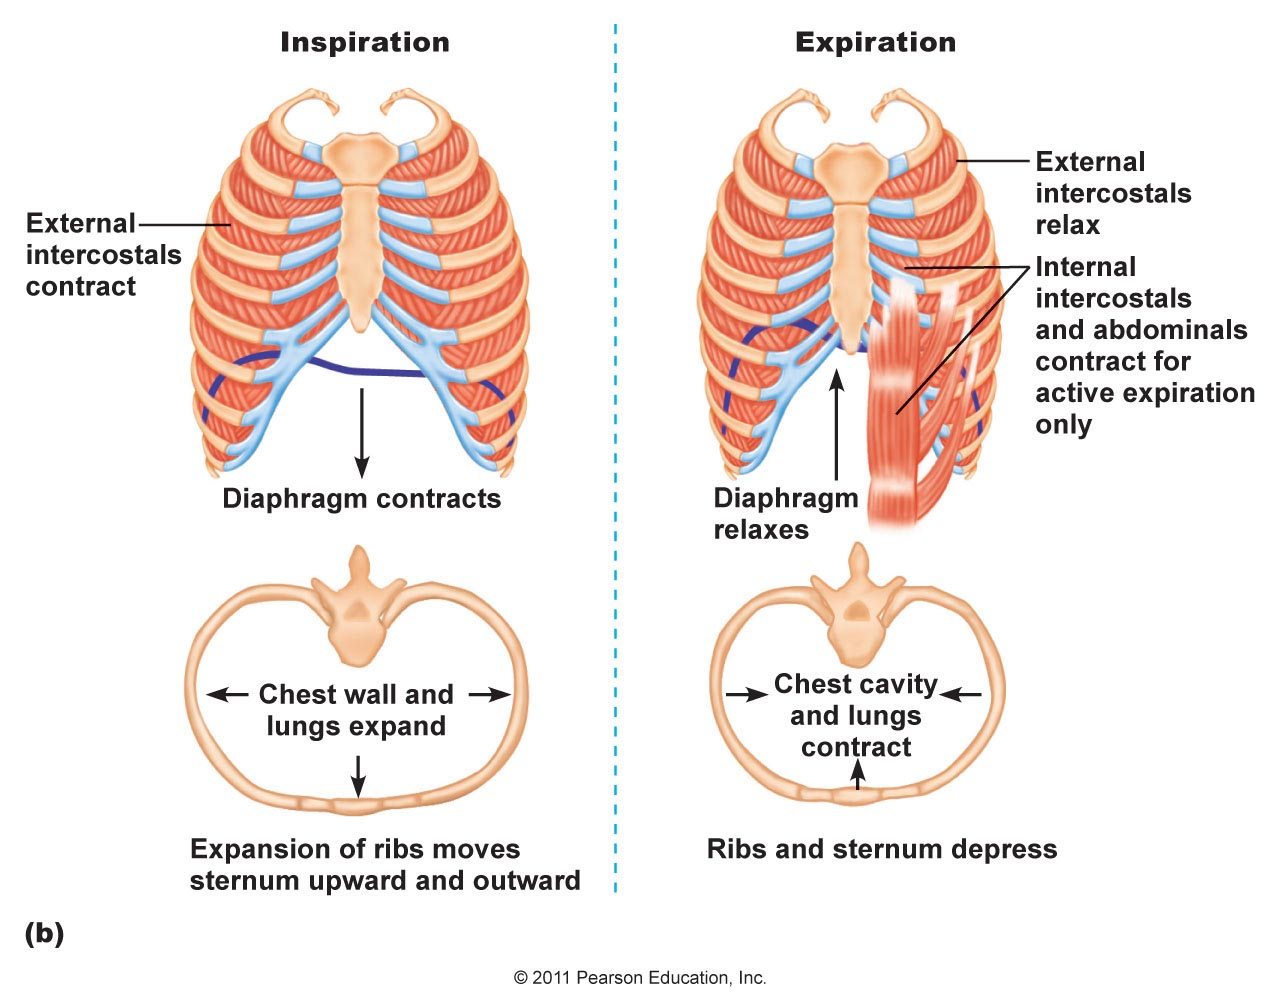

Normal Difference Between Chest Inspiration And Expiration

Normal Difference Between Chest Inspiration And Expiration

More picture related to Normal Difference Between Chest Inspiration And Expiration

Mechanism Of Breathing As Anatomical Process Explanation Outline

Mechanism Of Breathing As Anatomical Process Explanation Outline

Normal Difference Between Chest Inspiration And Expiration - 2025 DIY